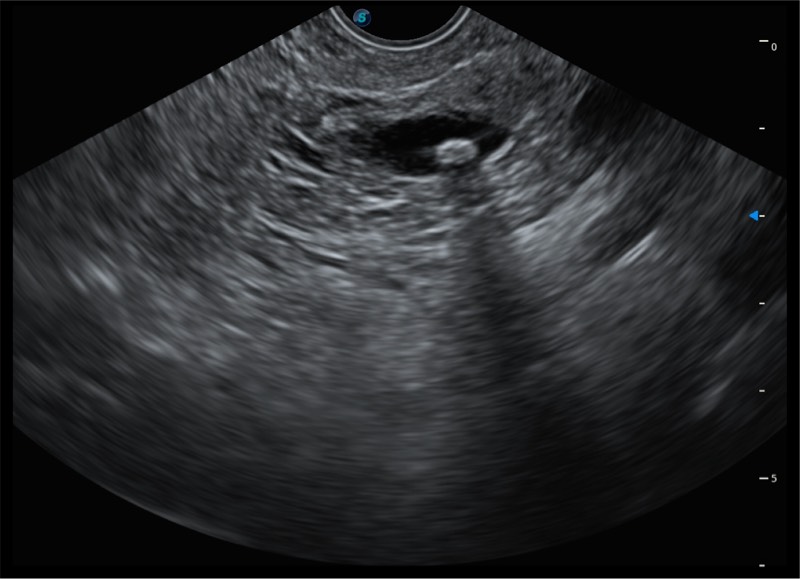

搭载百万级CMOS成像技术

及自主研发凸阵换能器,

可呈现优质的内镜和超声画面

基于二十年的超声技术积累,银河集团官网提供了最新一代的独立超声主机,在提供高质量图像的同时满足多学科使用。具备常见多普勒技术并提供弹性成像、声学造影等高端影像技术。新一代传感器具有更强的抗干扰能力并减少图像伪影。